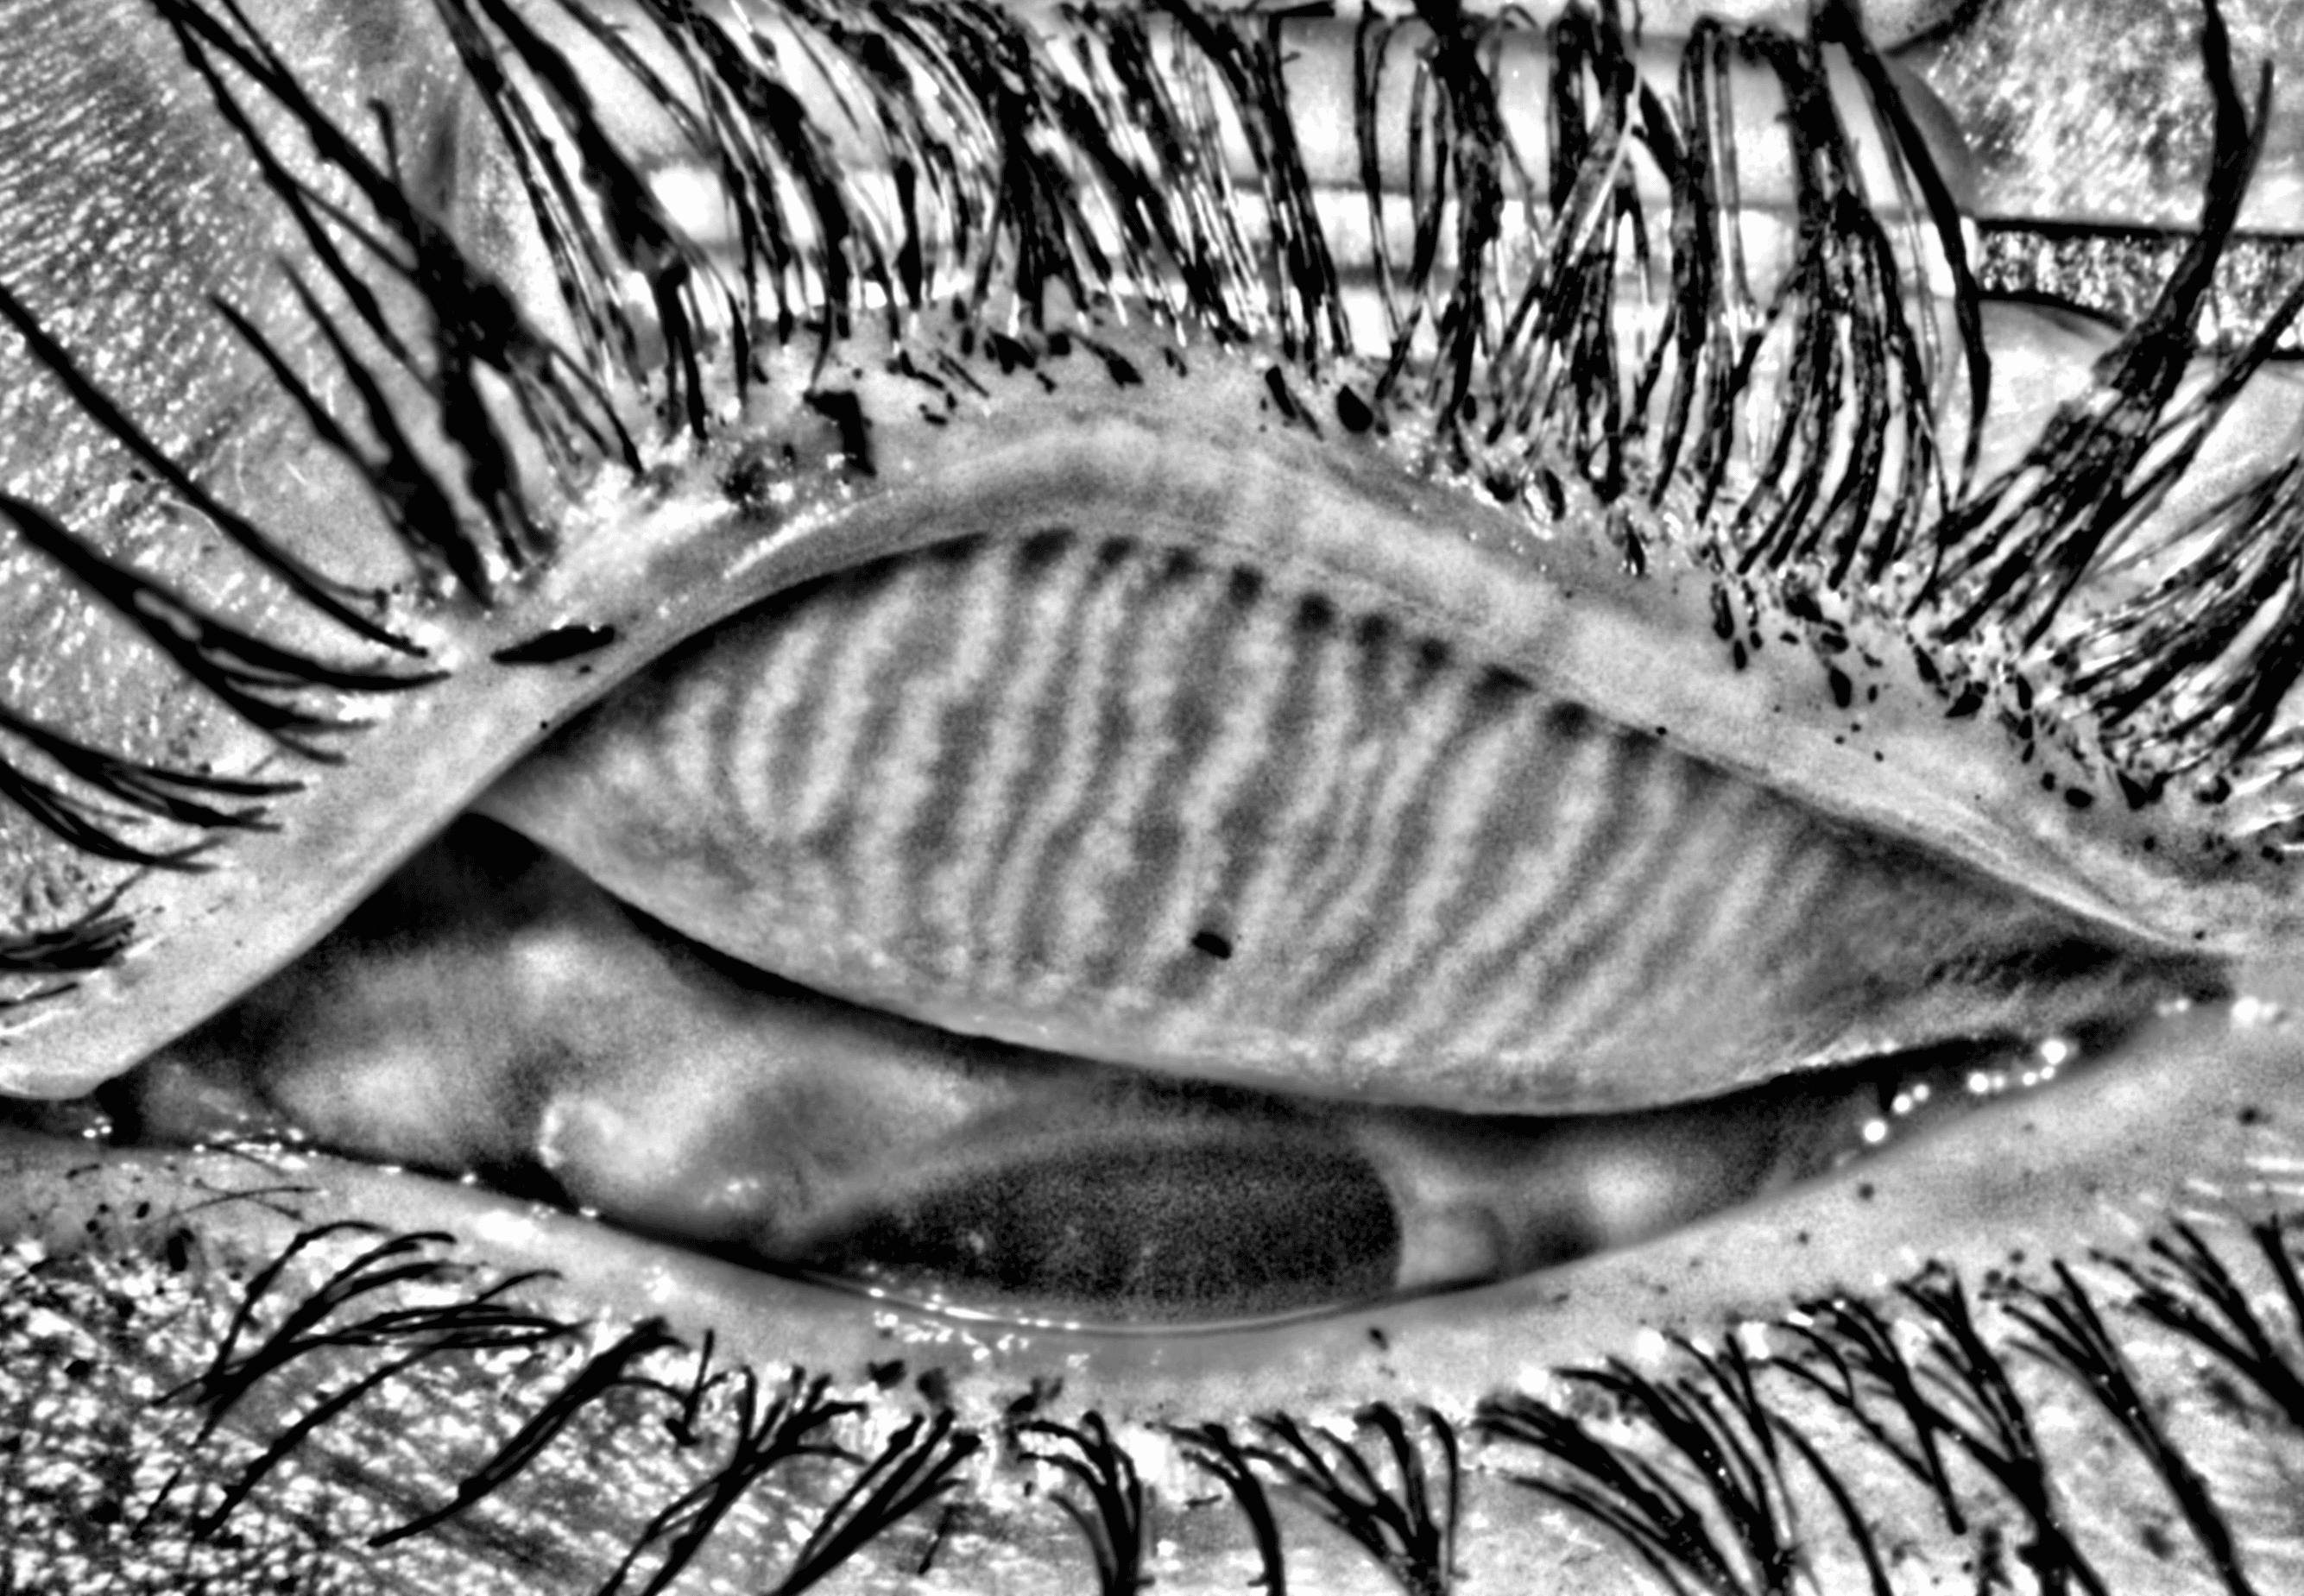

Capture and visualize meibomian gland structure, blink dynamics, tear film appearance, fluorescein imaging, and patient-reported symptoms using a single, compact device designed to integrate seamlessly into existing clinical setups.

See More with AI-Assisted

Real-Time Visualization

AI-assisted image processing enhances the visibility of ocular surface features, reducing time required manual image adjustments and allowing clinicians to focus on efficient clinical review. Operating directly on the live video stream, it provides immediate visual feedback that supports faster alignment, more confident image capture, and a smoother workflow.